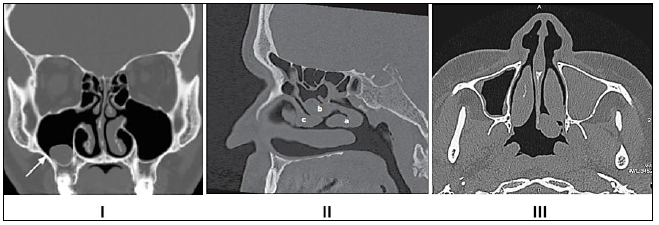

radiológicas é extremamente importante para materializar os preceitos anteriores. As imagens tomográficas

relacionadas a seguir apresentam-se em quais planos de corte?